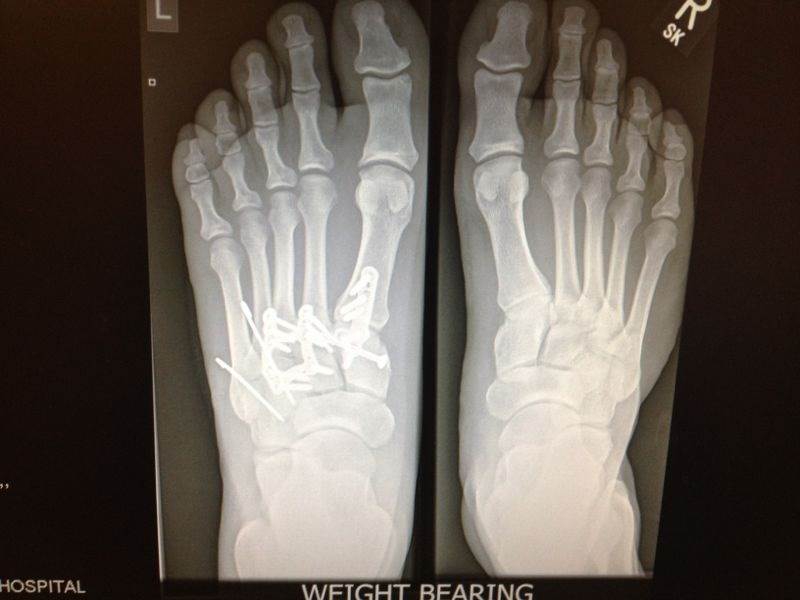

Actually he broke his foot, check out his new hardware, I see 15 screws, 3 plates, and 2 pins, at least.